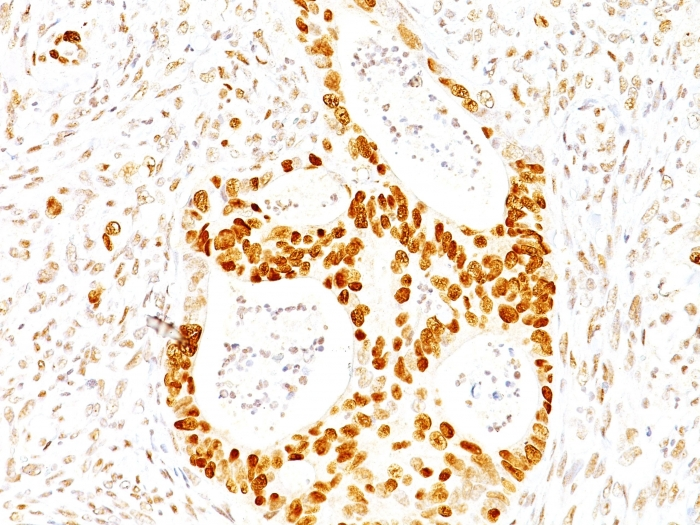

![IHC-P analysis of human colon carcinoma tissue using GTX34928 p27 Kip1 antibody [SX53G8]. IHC-P analysis of human colon carcinoma tissue using GTX34928 p27 Kip1 antibody [SX53G8].](https://www.genetex.com/upload/website/prouct_img/normal/GTX34928/GTX34928_20200115_IHC-P_487_w_23060801_167.webp)